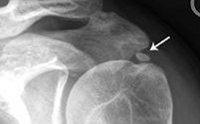

Типичным для гидроксиапатитной артропатии является выявление множественных кальцификатов в периартикулярных тканях при проведении рентгенографии позвоночника и суставов. При этом не наблюдается корреляция между количеством кальцификатов и выраженностью клинической картины. Выраженная клиника заболевания может сопровождаться отсутствием очагов кальцификации и, наоборот, выявленная рентгенологически кальцификация может не сопровождаться никакими проявлениями заболевания. Типичным является исчезновение кальцификатов после перенесенного приступа гидроксиапатитной артропатии.